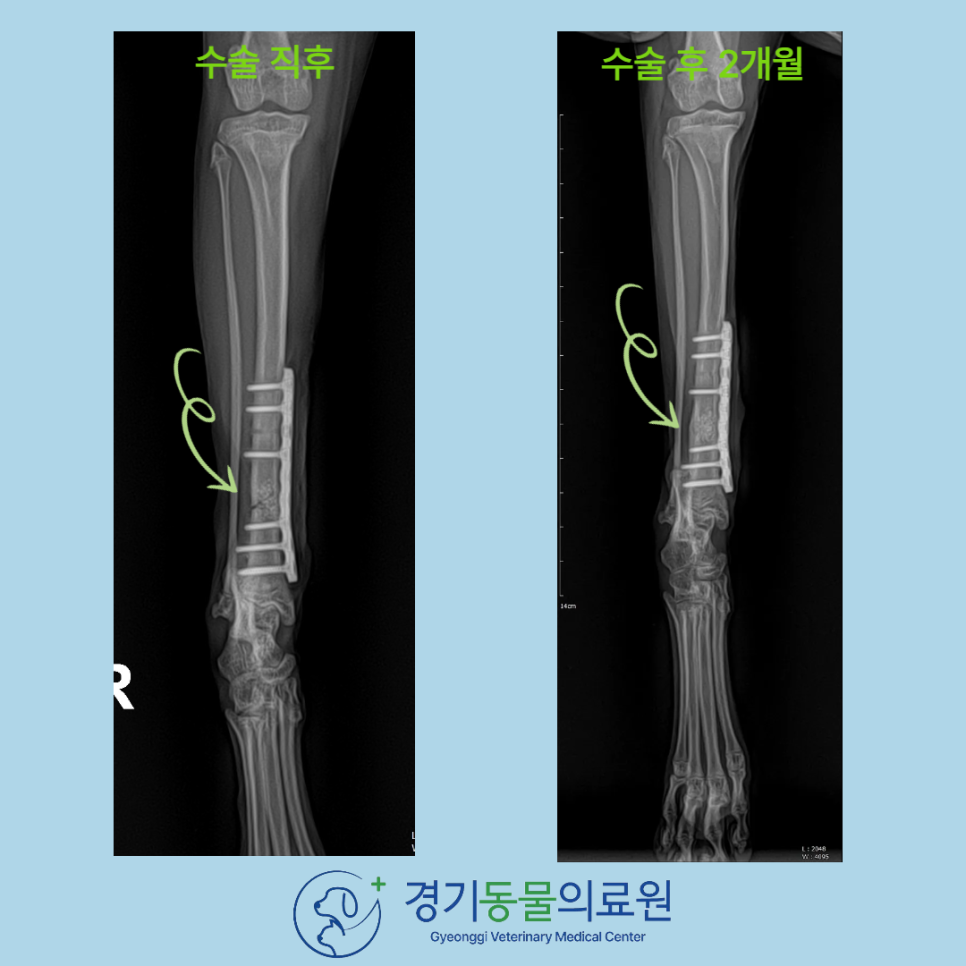

수술 후 X-ray 검사

경기동물의료원에서의 안전한 고양이 뒷다리 경골 골절 수술을 마친 후, X-ray 촬영을 통해 골절선이 보이지 않는 정도의 결과(화살표)를 확인할 수 있었습니다.

수술 후 이 냥이는 입원하며 통증 관리와 감염 예방 치료를 받았습니다.

수술 후 8주 차에 재진을 하려 내원했을때는 골유합 진행이 양호하였으며, 체중 부하 가능, 파행 증상 해소

가 확인되었습니다.